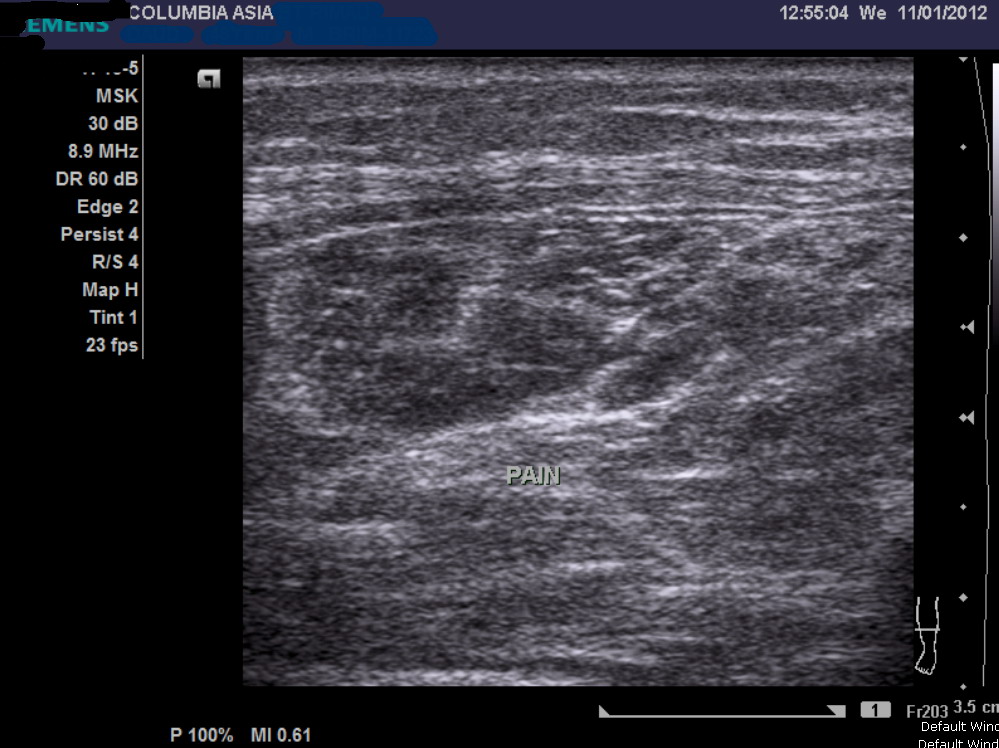

An ultrasound or MRI scan would help in this matter. I promptly sent him across the hallway to see the radiologist requesting for an ultrasound of his calf muscle, failing which we may proceed on to do a MRI scan.

The ultrasound report noted fluid/blood collection within the medial gastrocnemius (calf) muscle, which in the light of the patient’s history, confirmed the patient’s diagnosis:

Gastrocnemius muscle tear (calf tear)

As in this patient, the diagnosis can be confused with an achilles tendon rupture. However as explained above, palpation of the achilles tendon should demonstrate an intact tendon. In any case, imaging studies such as ultrasound and magnetic resonance imaging (MRI) can be useful to ascertain the diagnosis.